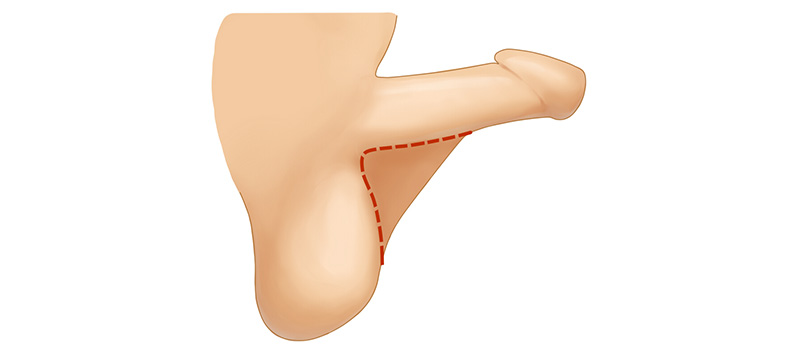

음낭갈퀴

음경에서 음낭으로 이어지는

피부가 마치 갈퀴모양처럼

발달되어 있는 경우

음낭갈퀴

음경에서 음낭으로 이어지는

피부가 발달되어 길이가 짧아 보이는 만큼

발달된 피부조직을 제거하는

수술을 통해 효과를 기대해볼 수 있습니다.